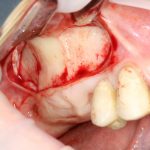

Вот клиническая картина через 4 месяца после ранее проведенной имплантации с остеопластикой:

Как видишь, коллеги из недалекой дружественной страны не осилили снятие швов. Мне это не нравится, хотя и объясняет, почему люди готовы ехать за тыщи километров ради 20-минутной операции удаления зуба мудрости.

Ну хорошо. Швы сняли. Делаем разрез. Обрати внимание, что после всех проведенных операций у нас остается очень небольшой по ширине слой жевательной слизистой оболочки: